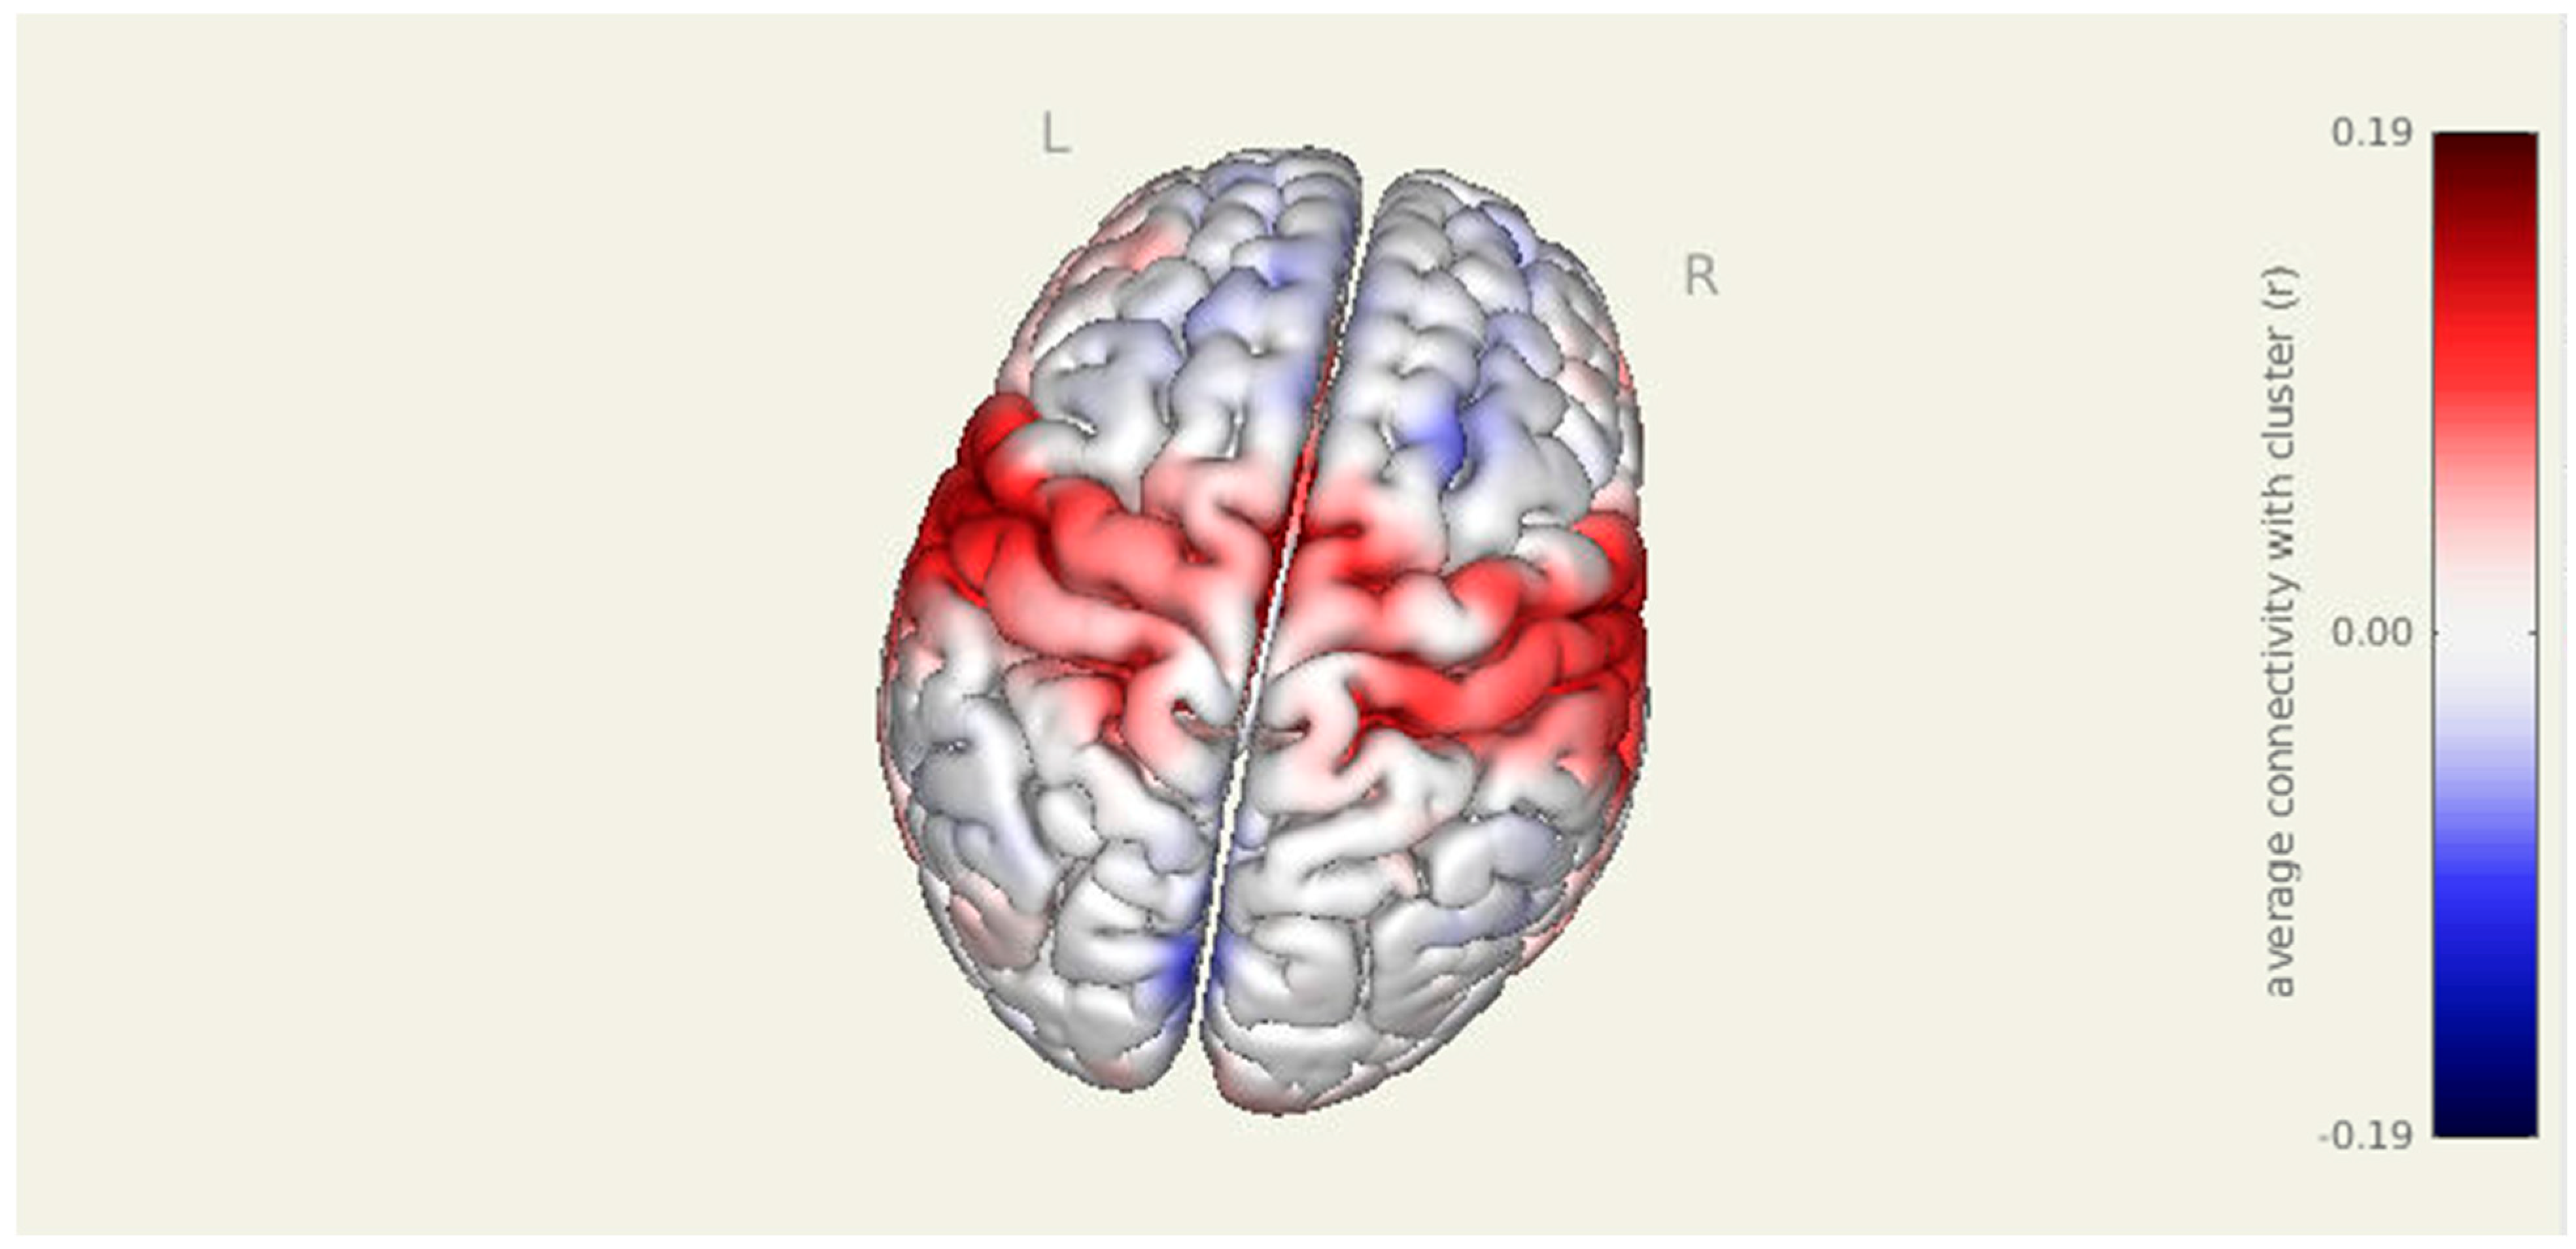

Figure 1.

Pre-intervention amygdala connectivity map. A 3D surface rendering illustrates widespread resting-state functional connectivity from the amygdala seed at baseline. Significant clusters were observed in bilateral cortical and subcortical regions, including the left parahippocampal gyrus, right superior parietal lobule, right insular cortex, and right thalamus (all p-FDR < 0.001).

3.2. Pre Amygdala Seed

Prior to intervention, seed-to-voxel analysis from the amygdala revealed widespread connectivity with multiple cortical and subcortical regions (Figure 1). Significant clusters were observed in bilateral sensorimotor and frontal areas, including the left parahippocampal gyrus (MNI: −36, +06, −28; cluster size = 1396 voxels; p-FDR < 0.001), right superior parietal lobule (+38, −56, +60; 575 voxels; p-FDR < 0.001), right insular cortex (+46, −06, +16; 406 voxels; p-FDR < 0.001), and right thalamus (+18, +10, −16; 383 voxels; p-FDR < 0.001). Additional clusters were detected in the left superior parietal lobule, right cerebellum, and prefrontal cortex, further supporting elevated amygdala connectivity within regions implicated in sensory integration, emotional processing, and motor readiness (Figure 2).